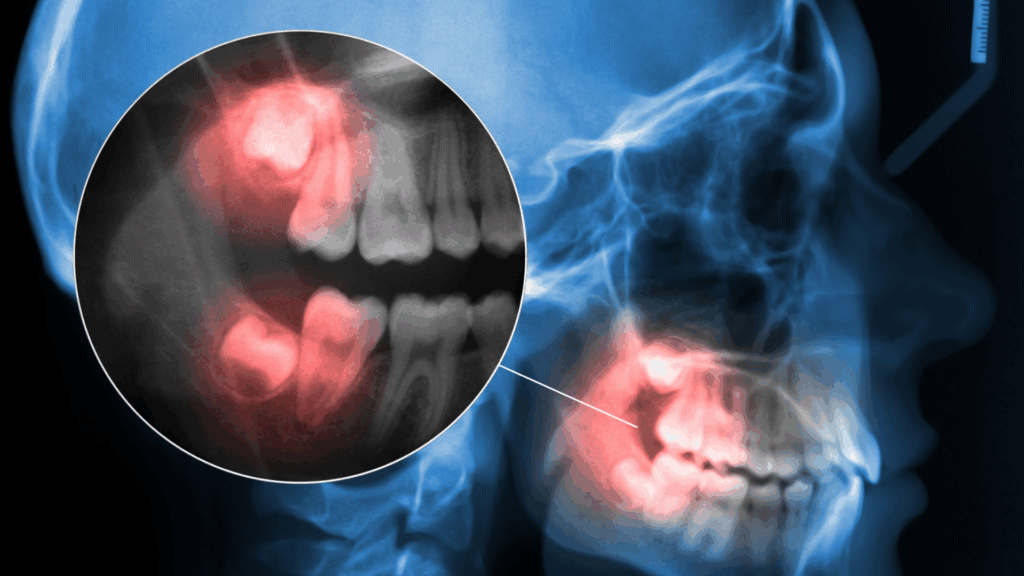

For many teens and young adults, wisdom tooth removal feels like a rite of passage. Just hearing the words “wisdom tooth extraction” can make people nervous, often because of stories they’ve heard from friends or family. While wisdom teeth sit at the very back of the mouth and can help with chewing when they come … Continued